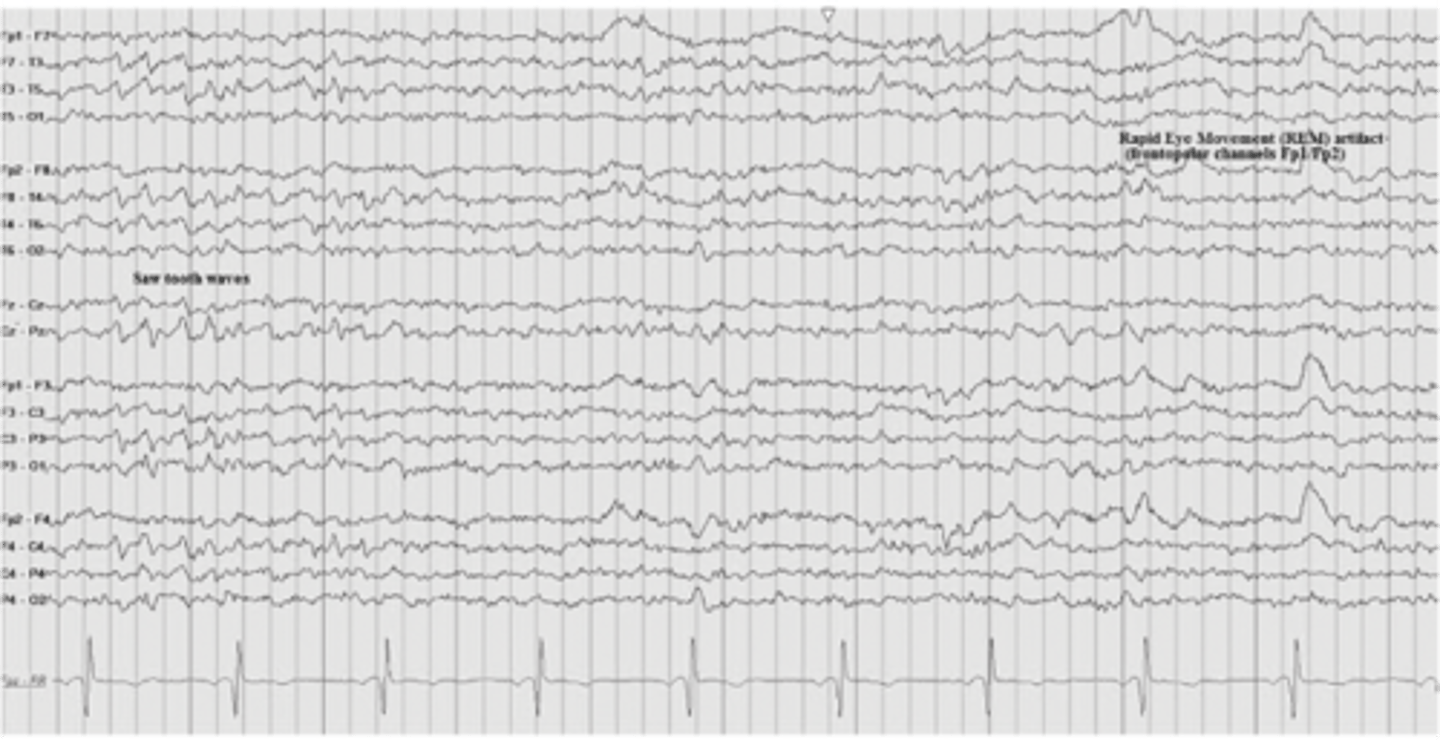

EEG measures the pattern of

electrical activity in the brain

EEG can find brain wave patterns a/w

epilepsy, seizure, tumors, alzheimer disease, psychoses, sleep disorders, brain injury/death

brain death on EEG

normal EEG